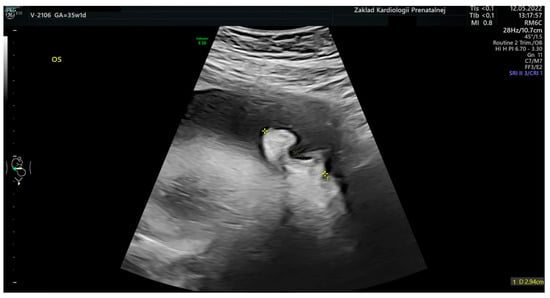

An image of a fetal ear in 2D ultrasound examination. Measurement of the fetal ear at the gestational age of 35 weeks and 1 day.

Figure 9.

An image of a fetal ear auricle in 3D ultrasound examination at the gestational age of 35 weeks and 1 day. A genetic test of the amniotic fluid: the use of whole genome oligonucleotide microarrays (CytoSure Constitutional v3 (8x60k), Oxford Gene Technology, GRCh37/hg19) with an average resolution of 120 kpz–arr(X,Y)x1,(1-22)x2–No abnormalities were detected.

Figure 10.

A postnatal image of an ear auricle from Figure 9. The 2D measurement was within normal range; however, the shape of the ear auricle is grossly abnormal.

The range of fetal ear length measurement in healthy fetuses in the gestational age of 17.0 to 39.5 weeks according to the last menstrual period is 10.00–40.00 mm. In the second trimester of pregnancy, the range of fetal ear length measurement is 18.00–28.00 mm, whereas in the third trimester of pregnancy, the range is 16.00–40.00 mm. The R-value of 80.53% and R2 value of 64.84% show a good correlation between gestational age and fetal ear length. What must be emphasized is that the fetal ear measurement can fall within the normal range even if there are some genetic or non-genetic disorders. That is why the fetal ear measurement does not provide any diagnostic value in terms of detection of any fetal genetic and non-genetic disorders. A good example is presented in Figure 9 (prenatal imaging) and Figure 10 (postnatal follow-up). This is an example of a newborn with an abnormal shape of the fetal ear auricle even though the newborn does not present any genetic abnormalities, which was confirmed in a genetic test of the amniotic fluid at the 22nd week of pregnancy with the use of the whole genome oligonucleotide microarrays (CytoSure Constitutional v3 (8x60k), Oxford Gene Technology, GRCh37/hg19) with an average resolution of 120 kpz–arr(X,Y)x1,(1-22)x2–correct result (test number: aCGH-PD10038, DNA number: PD10038). The genetic test was performed at a leading genetic clinic in Poland. This confirms our conclusion that fetal ear measurement has no clinical value. Even if fetuses with Down syndrome have a smaller fetal ear [,] compared to fetuses without any disorders, in this study, the authors do not support such observations in relation to fetuses with trisomy 21.